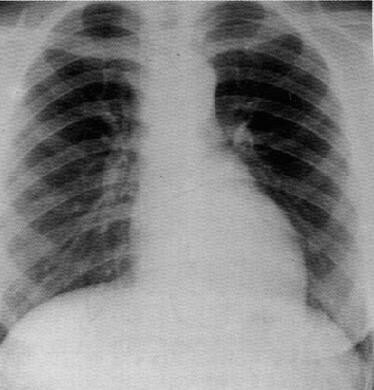

as_cxr.jpg (21481 bytes)    Рентгенограмма б-го Р

Дуга аорты приподнята до 1 межреберья, признаки систолической гипертрофии левого желудочка.